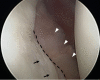

Glenoid articular cartilage lesion is a rare complication following traumatic anterior dislocation of the shoulder. We report the case of a 14-year-old male rugby player with traumatic anterior shoulder instability, an extensively flapped lesion on the glenoid articular cartilage, and an osseous Bankart lesion. Arthroscopic findings revealed that the glenoid cartilage was flap-detached, extending from the anteroinferior to the center. Repair of the osseous Bankart lesion using suture anchors and resection of the unstable peripheral part of the cartilage was performed arthroscopically. The main region of the injured articular surface was left untouched. During postoperative follow-up, absorption of the glenoid articular surface near the suture anchor holes was identified. Arthroscopic examination three months post-surgery showed that the flap detached lesion of the residual cartilage was stable and appeared adapted on the glenoid surface. The resected area was covered by fibrous tissue. A follow-up computed tomography scan revealed that the osseous lesion was united. The patient returned to his previous sports capacity eight months following the operation. At the 2-year-follow-up, magnetic resonance imaging revealed that the glenoid surface was remodeled to a flattened round shape with no signs of osteoarthritis, exhibiting proper conformity of the joint surfaces to the humeral head. Arthroscopic Bankart repair using suture anchors may cause bone resorption at the glenoid surface, leading to remodeling of the glenoid surface from the damaged glenoid cartilage lesion in young patients.